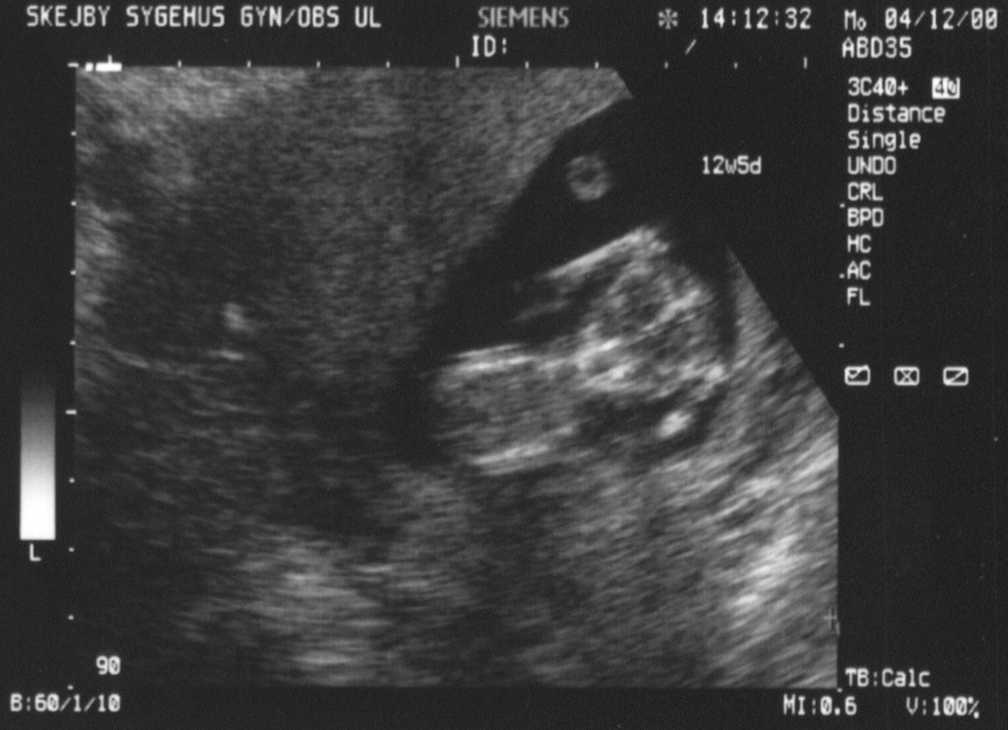

Scannings at the 12th and 19th week of the pregnancy.

Full picture from scanning in the 12th week. Lots of life and movement in there. Same picture, but with explanations. It takes a bit of practice to see anything on these images. Facial shot - looks eerie, but she was looking all the time curiously at the scanner. Really detailed - even though she's 12 cm from head to butt here. Same picture, but with explanations. Sorry, it's all in danish.